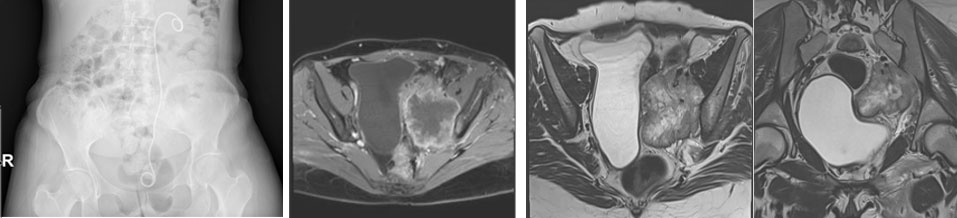

Ameliyat öncesi: Röntgende sol üreterde katater dışında anlamlı görüntü yok iken MR’da sol sakroiliak eklem seviyesinde düzensiz sınırlı içinde gaz gölgesi olan ve mesaneyi iten büyük yumuşak doku kitlesi görülmekte